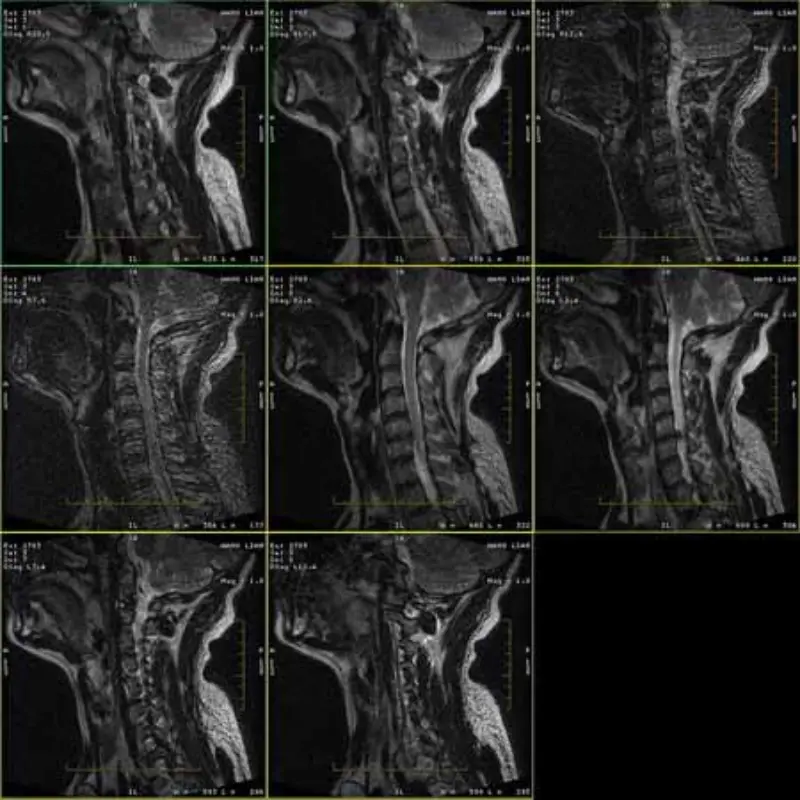

Obrázky protokolov FRFSE a GRE majú duch a niekedy sa v jednej sérii objavia obrázky s nízkym SNR. Ale obrázky protokolu SE sú normálne.

Pozrite si priložené obrázky.